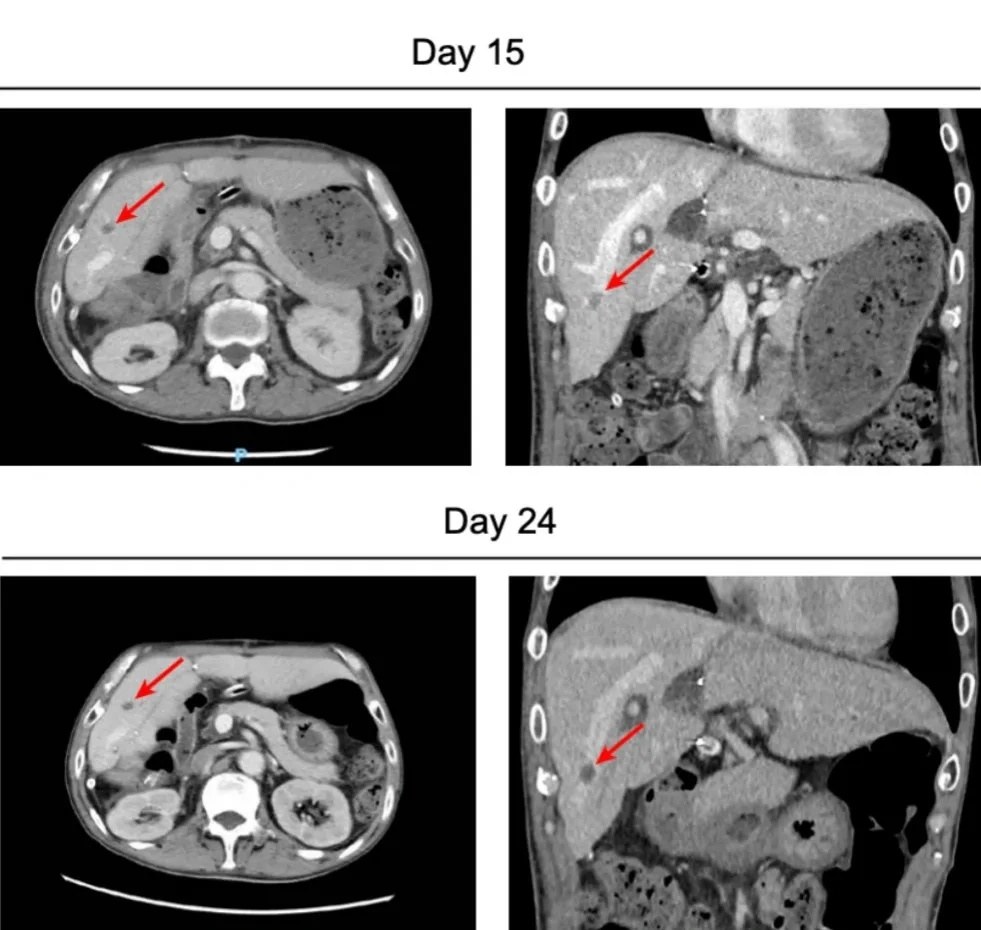

不良反应1:血栓形成

术后早期,患者即出现纤维蛋白/纤维蛋白原降解产物(FDP)和D-二聚体水平的持续升高,虽然持续使用依诺肝素进行抗凝治疗以预防血栓,但CT显示,移植后的猪肝内肝静脉末端有一小结节性血栓。

图源:参考资料1